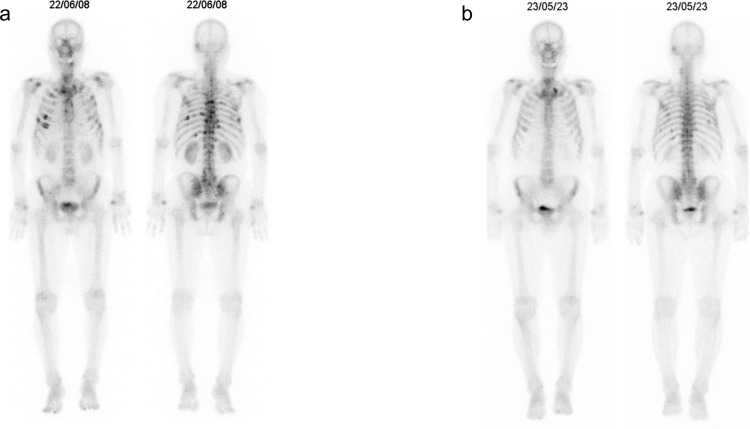

Immune checkpoint inhibitor-related thrombocytopenia (irTCP) is a relatively rare immune-related adverse event (irAE); however, overall survival may worsen when it occurs. Prolonged use of high-dose steroids can diminish the effectiveness of immune checkpoint inhibitor (ICI) therapy on the primary disease because of T lymphocyte suppression, thus early tapering is necessary. We experienced a rare case of a 79-year-old male who concurrently developed irTCP and multiple myeloma (MM) during treatment with ICIs for lung adenocarcinoma. The patient exhibited severe thrombocytopenia and elevated serum IgA levels. Based on various tests, we diagnosed MM and irTCP. Despite administering the standard bortezomib plus dexamethasone (Bd therapy) treatment for MM, there was no response and the irTCP was steroid-resistant. Consequently, we administered a regimen including daratumumab (DPd therapy) for steroid-resistant irTCP and refractory MM, which resulted in a response. As a result, we were able to avoid prolonged use of high-dose steroids and the patient is stable without exacerbation of lung adenocarcinoma for 1 year and 5 months after the onset of MM. To our knowledge, there are no cases of MM developing during ICI treatment and this is the first case report in which daratumumab was effective for the treatment of irTCP.